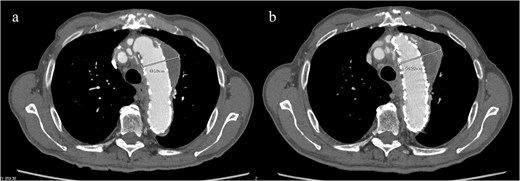

Given the ongoing hemoptysis, presumed aneurysmal expansion due to an occult endoleak, and the absence of any other obvious causes of hemoptysis, we determined that intervention for the aneurysm was necessary. TEVAR was performed using a right femoral artery approach. Initial angiography did not reveal contrast leakage into the sac (Fig. 3a). A 34 × 34 × 200 mm Gore Conformable TAG stent graft (W.L. Gore & Associates, Flagstaff, AZ, USA) was deployed to cover the distal edge of the FET. The second stent graft, a 34 × 34 × 150 mm Gore Conformable TAG stent graft, was deployed overlapping the first graft immediately after the left subclavian artery branch to cover the entire length of the FET (Fig. 3b). Considering the proximal migration, a type Ib endoleak was deemed the most likely cause. However, the possibility of a type III endoleak from the graft was also considered, so the stent graft was deployed to cover the entire area. The patient’s hemoptysis resolved completely postoperatively. A follow-up CT 2 years later showed a reduction in the aneurysm size from 56 to 44 mm (Fig. 4).

(a) Angiography performed from within the FET before deploying the stent graft showing no evidence of endoleak or aortobronchial fistula. (b) Angiography after stent graft placement. The bidirectional arrow shows the original extent of the FET insertion.